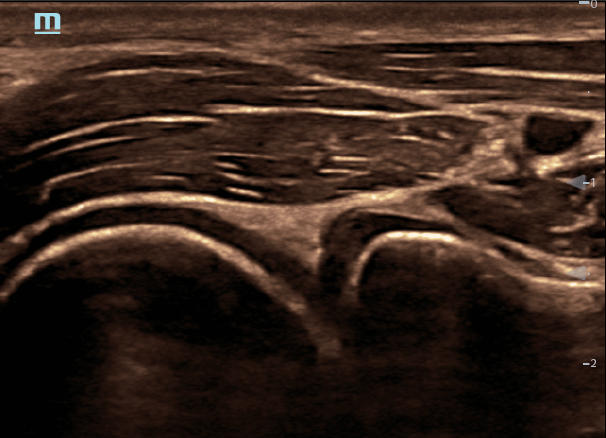

Ultrasound Reimagined

Advanced Technologies

Clinical Certainty Within Reach